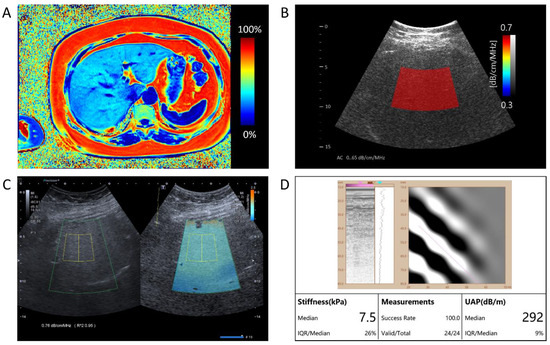

For each patient, after the B-mode ultrasound examination, the same radiologist performed additional ultrasound examinations on the same day. Each session was performed using three different ultrasound examination platforms: QUS-AC (dB/cm/MHz) using Vantage 64LE (Verasonics, Inc., Kirkland, WA, USA) ultrasound system (Figure 2B), ATI (dB/cm/MHz) using Aplio i900 (Canon Medical System, Tochigi, Japan) (Figure 2C), and UAP (dB/m) using FT100 (FibroTouch, Wuxi, Jiangsu, China) (Figure 2D).

The PDFF images were reconstructed offline using a complex-based water–fat separation algorithm. This algorithm estimates the PDFF, which measures the proportion of the fat signal relative to the total signal (water and fat) in each voxel. The PDFF maps were used to quantify liver fat and are expressed as a percentage (%) (Figure 2A).

In this paper, we propose an AI-based quantitative ultrasound algorithm that estimates the AC of liver parenchyma from the captured ultrasound signals. To mitigate the decrease in accuracy caused by ultrasound noise reflected from tissues other than the liver and reduce measurement variation among users, the proposed AI-based algorithm adaptively selects the parenchymal area of the liver from B-mode images and derives the AC values using only ultrasound signals reflected from the liver parenchyma (Figure 2B).

2.4. Attenuation Imaging

2.5. UAP and Stiffness Assessment

UAP was obtained using the FT100 (FibroTouch, Wuxi, Jiangu, China). The 3.5 MHz M probe was used. The FibroTouch estimates both liver stiffness in kiloPascals (kPa) and liver attenuation coefficient in decibels/meters (dB/m) (Figure 2D).

Figure 2. A comprehensive assessment of hepatic fat content in a single patient. (A) The representation of Magnetic Resonance Imaging-Proton Density Fat Fraction (MRI-PDFF) presents a measured value of 31.59%, quantifying the level of hepatic steatosis. (B) The AI-enhanced quantitative ultrasound attenuation coefficient (QUS-AC), quantified as 0.65 dB/cm/MHz, demonstrates the AI-based quantitative ultrasound assessment of fatty liver. (C) The Canon ATI returns an attenuation value of 0.76 dB/cm/MHz. (D) The FibroTouch UAP returns an attenuation value of 292 dB/m.